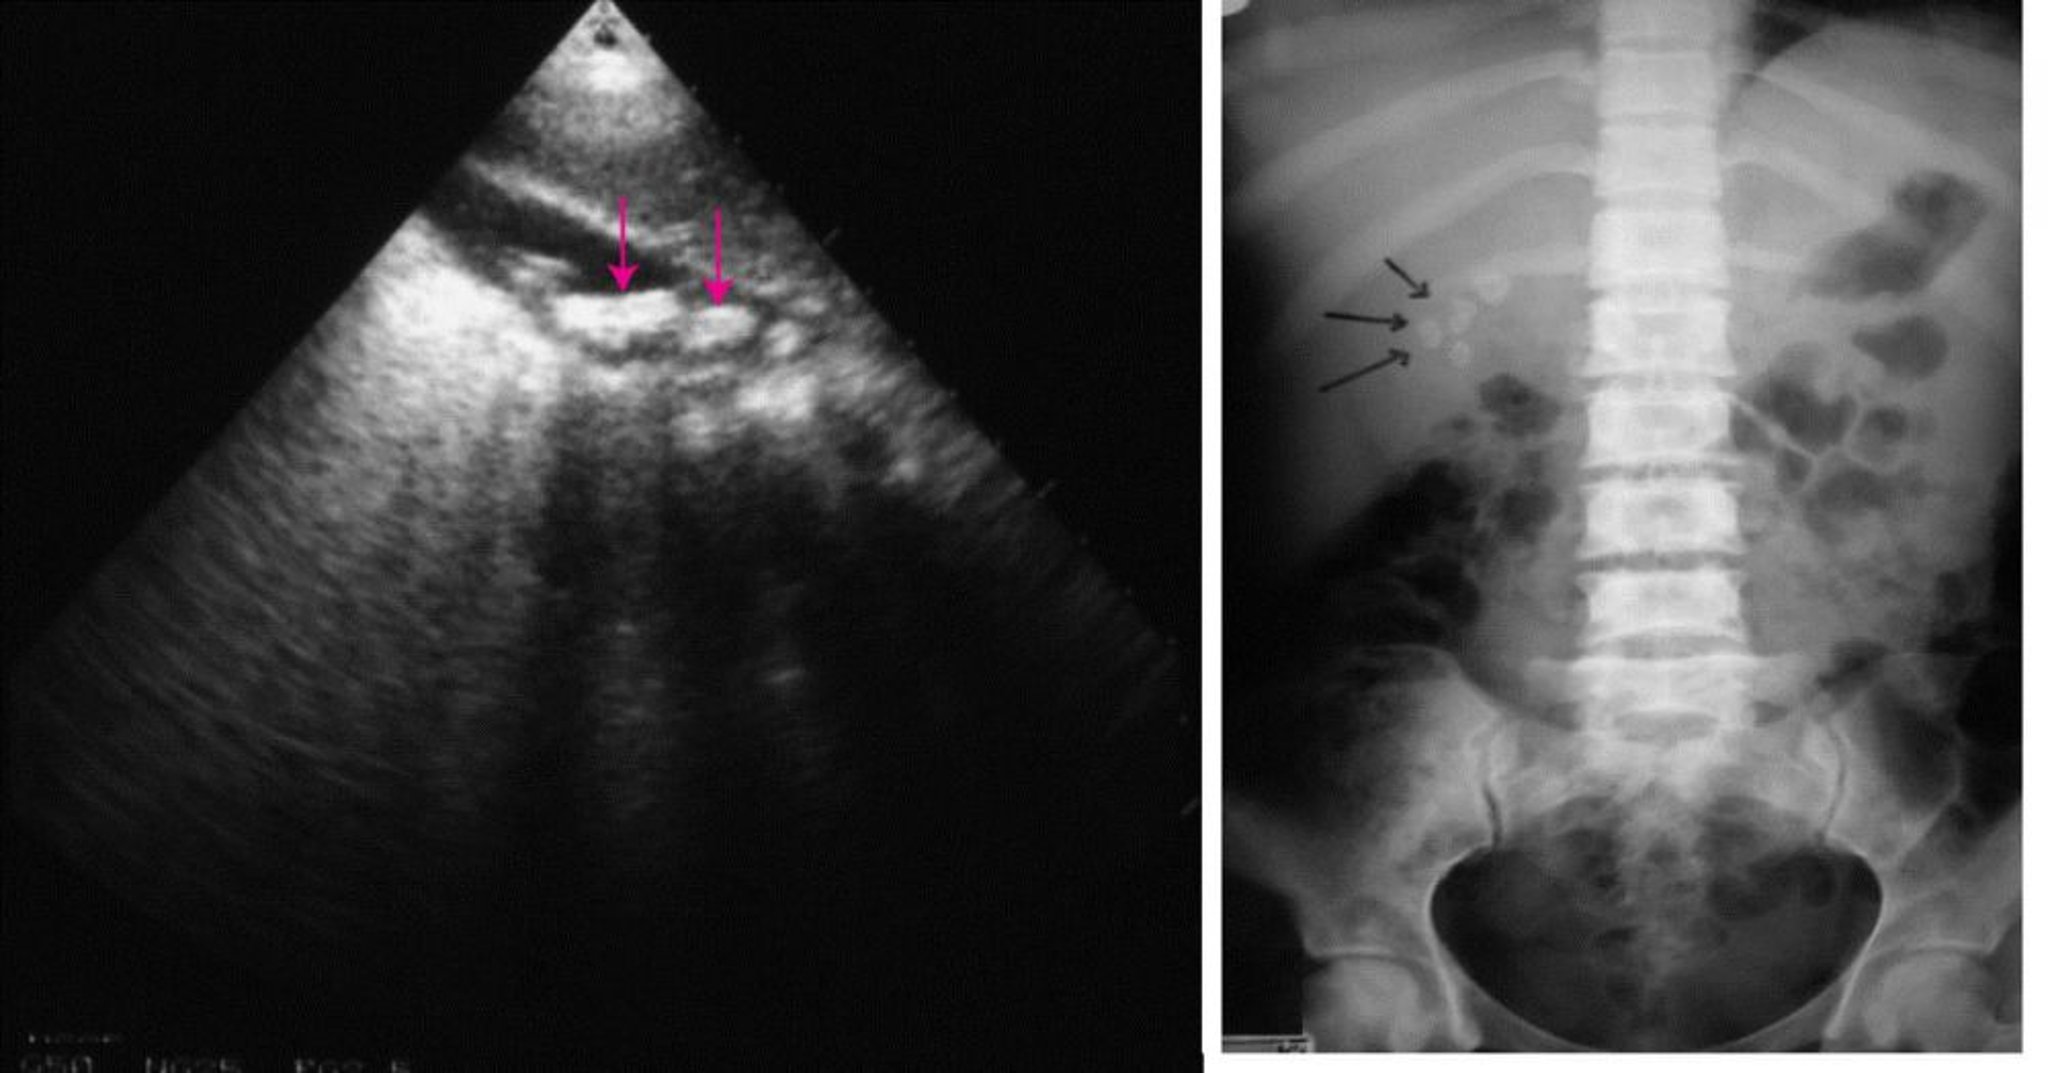

Ở bên trái, siêu âm ổ bụng cho thấy có nhiều sỏi mật (hình mũi tên). Ở bên phải, chụp X-quang ổ bụng thông thường cho thấy sỏi mật chắn bức xạ (hình mũi tên).